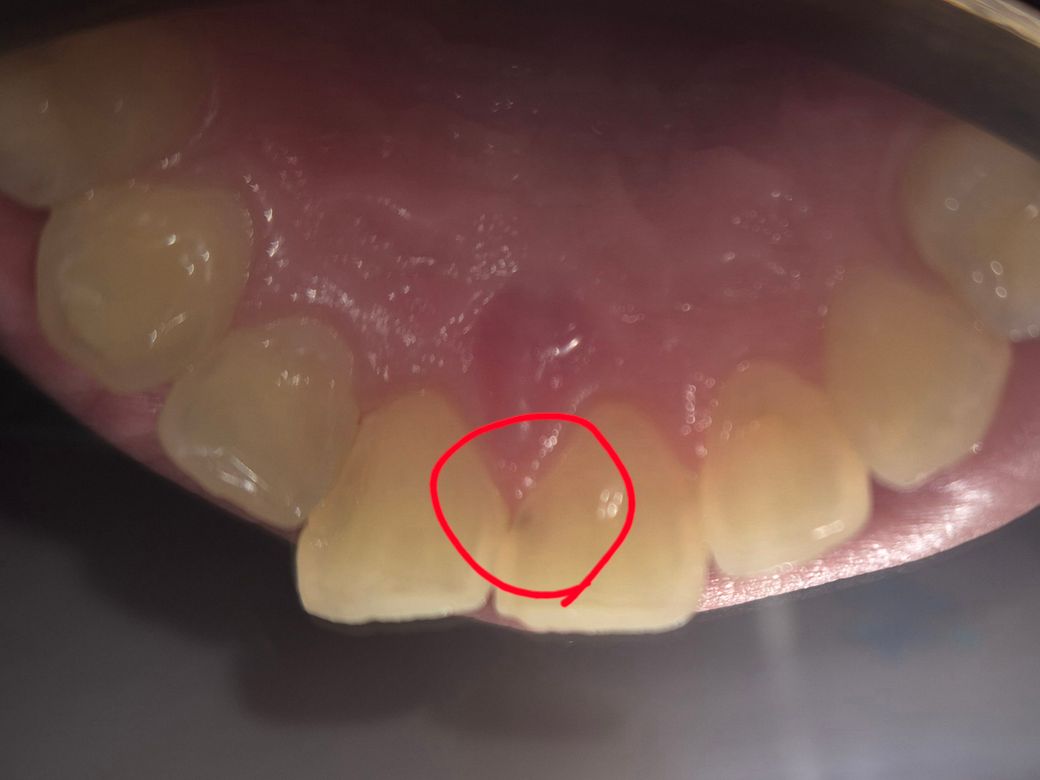

앞니 조금 보이는 충치 치료 해야되나요?

오늘 치과에 가서 발견을 했는데

있는지도 몰랐고, 아프지도 않은데 꼭

치료를 해야할까요.

많아 파내야 할까봐 걱정이 됩니다...

• 1번 째 사진

옆쪽 충치는 빠르게 진행되는 특성이 있어서 신경치료가 필요할정도로 충치가 커질 수도 있습니다 엑스레이도 한번 찍어보고 판단하면 되겠습니다

충치가 육안상으로 보이는거 같습니다. 엑스레이를 찍어보시고 치료를 하시는게 좋을것같습니다.